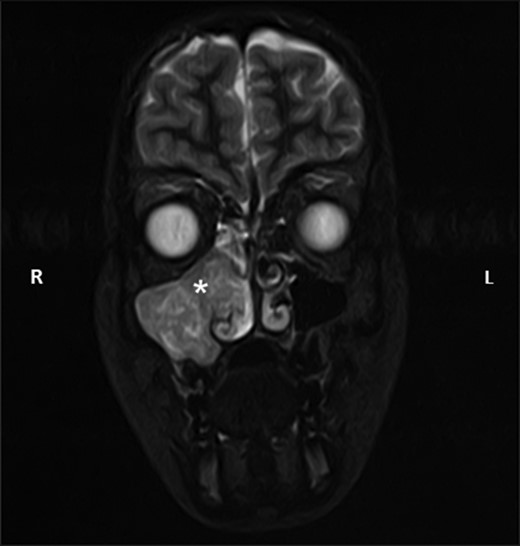

Computerized tomography (CT) and magnetic resonance imaging (MRI) confirmed the presence of a large right-sided sinonasal mass extending posteriorly to the nasopharynx. Irregularity was noted along the posterolateral wall of the maxillary sinus (Figs 1 and 2). In view of the age, sex and clinical presentation, a provisional diagnosis of juvenile nasopharyngeal angiofibroma (JNA) was made.

Coronal STIR sequence magnetic resonance image taken as part of the diagnostic investigations, showing the same antrochoanal mass (white asterisk) showing extension into the nasal cavity. L, left; R, right.